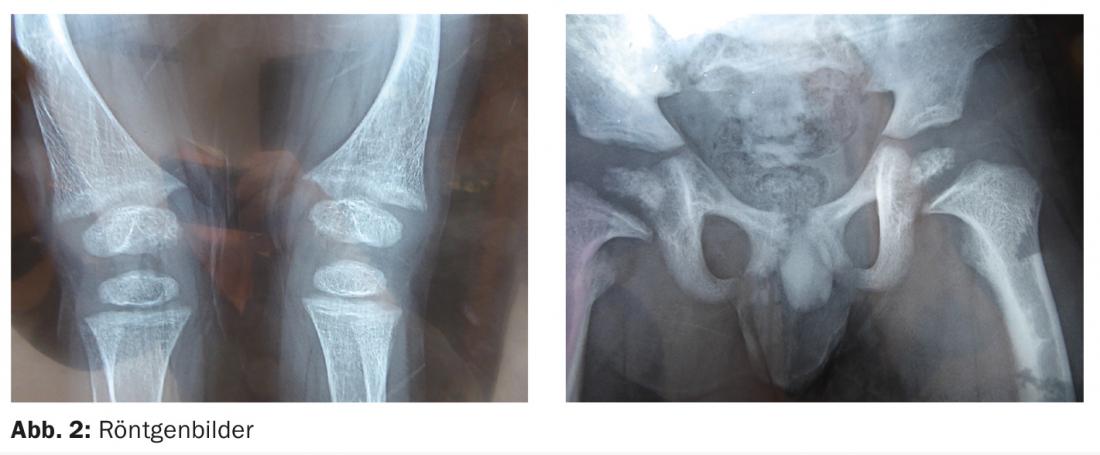

El primer contacto tuvo lugar en Ecuador en julio de 2015. Las imágenes de rayos X ya estaban disponibles en ese momento (Fig. 2), pero datan de 2012.

Los fémures están curvados váricamente, hay una coxa vara en ambos lados. Las metáfisis distales de los fémures están distendidas, algo menos las tibiales proximales.